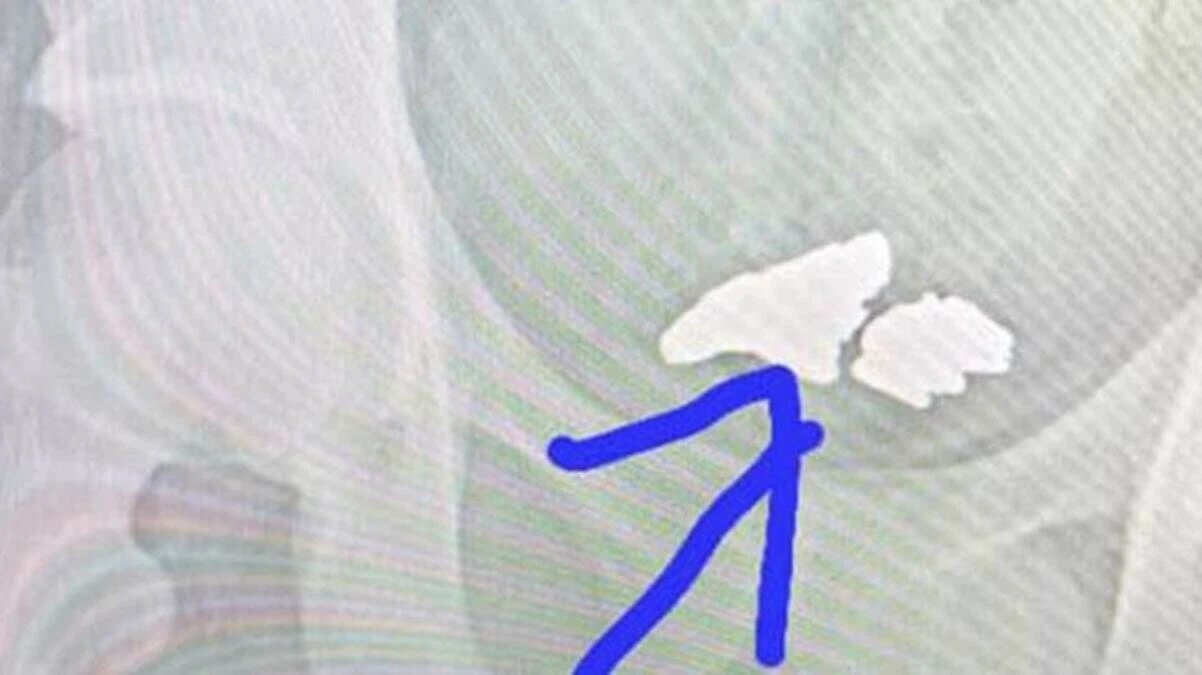

Doktorlar, şiddetli karın ağrısıyla gelen işçiye röntgen çekince ise şoke oldular. İşçinin midesinde 81 gramlık altın röntgenle gün yüzüne çıktı. Doktorlar, polise haber verirken altın doğal yöntemlerle işçiden çıkarıldı.